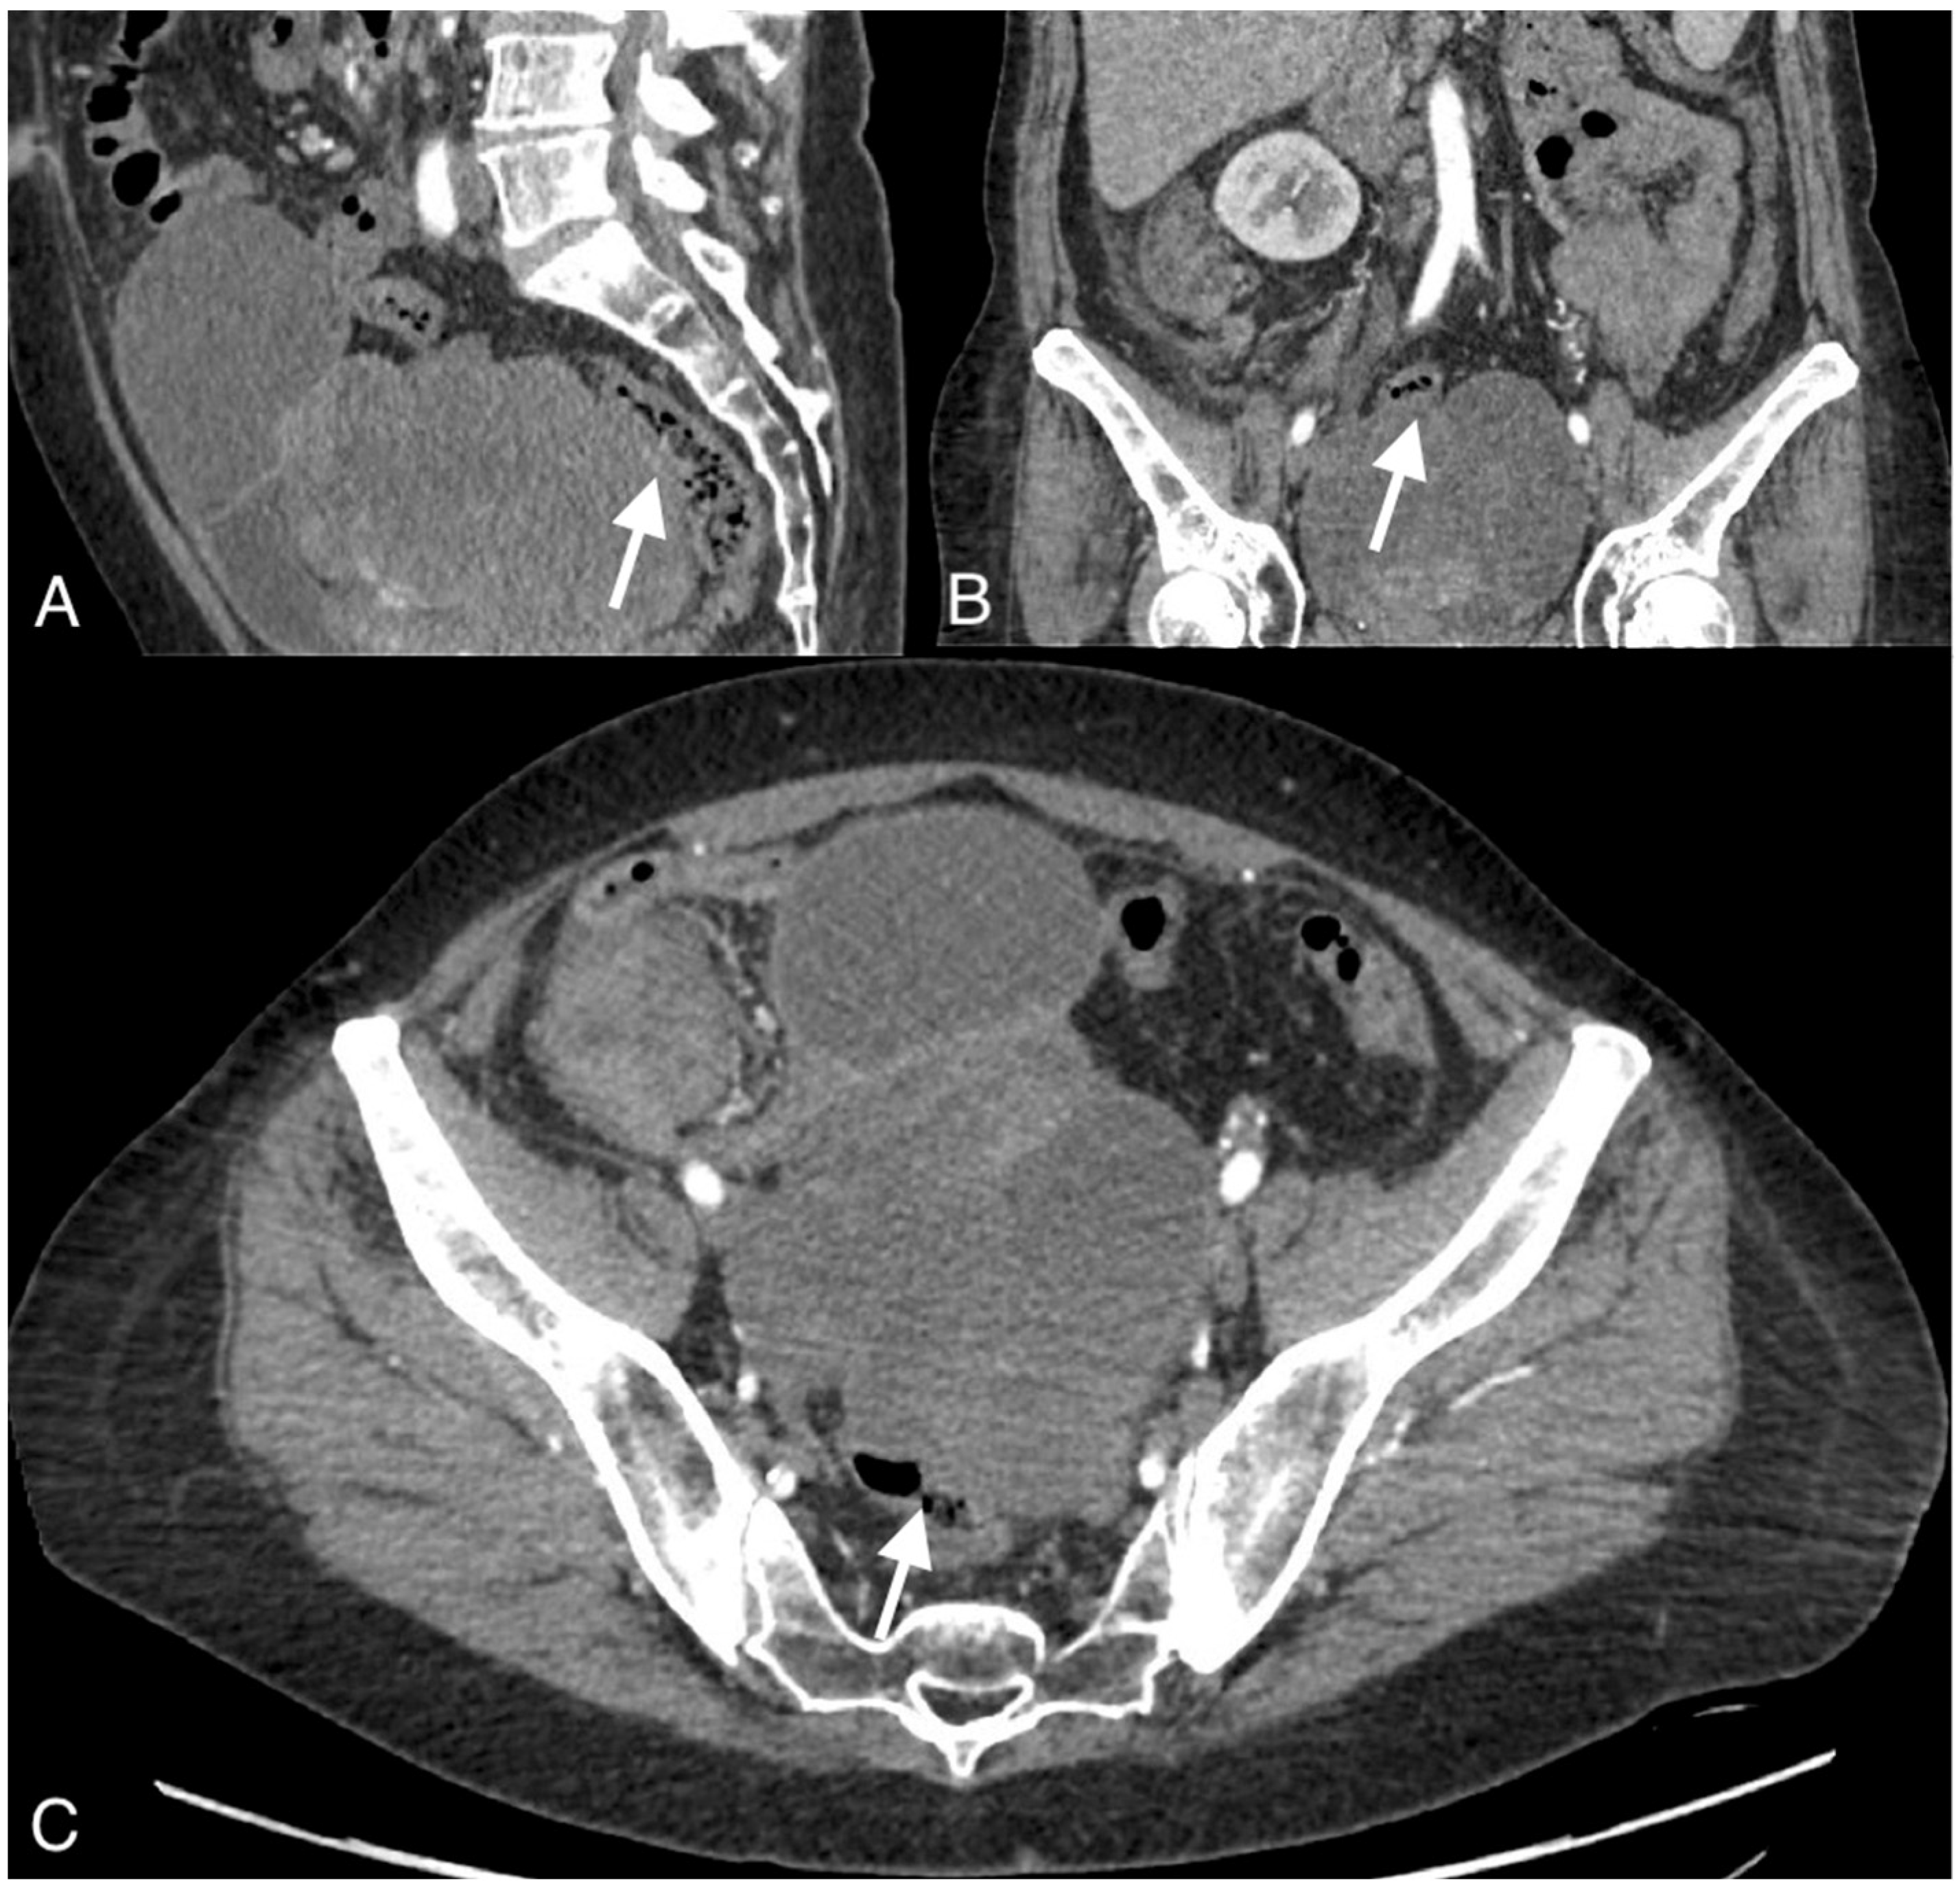

3.1. Imaging Findings